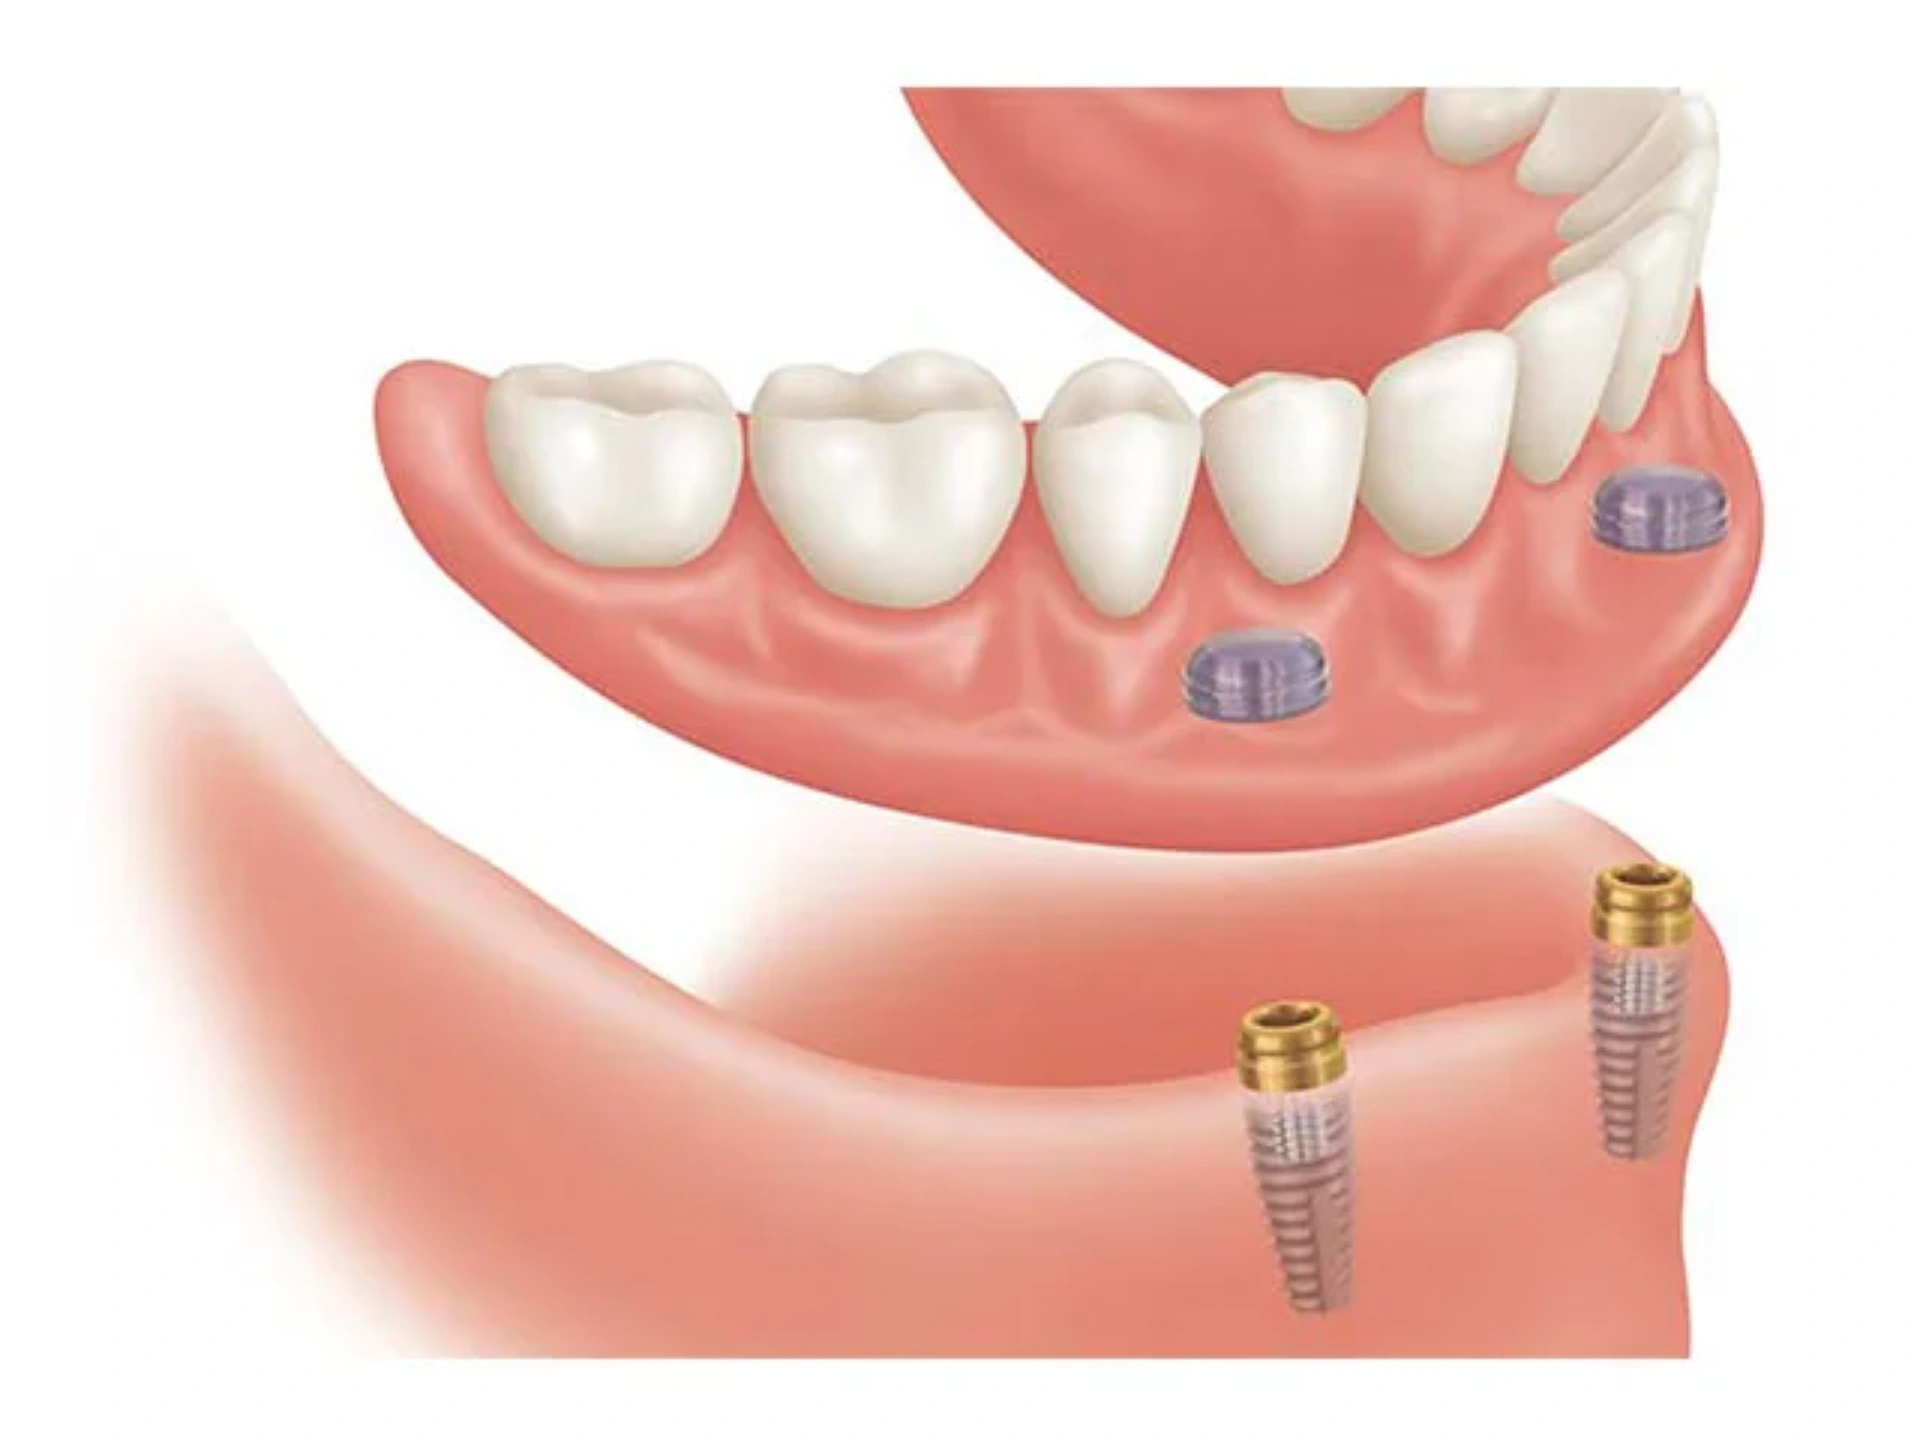

Tam Hərəkətli Protezler: Bütün dişlərin itirildiyi (edentulous) hallarda istifadə edilir. Üst və alt ...

Diş İmplantasiyası Prosedurunun Əsas Mərhələləri: Planlaşdırma: İmplantasiya üçün ətraflı diş və ...